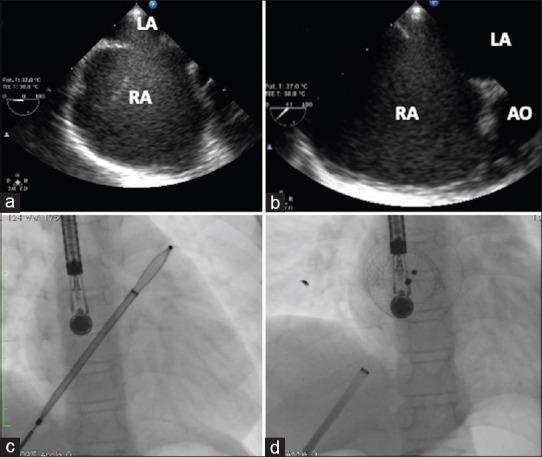

Transhepatic device closure of atrial septal defect in children associated with interrupted inferior vena cava.

Ann Pediatr Cardiol. 2022 Mar-Apr;15(2):160-163. doi: 10.4103/apc.apc_228_21. Epub 2022 Aug 19.

Abstract

Percutaneous transcatheter closure of fossa ovalis atrial septal defect (FOASD) is an established procedure. When femoral venous approach is unfeasible due to interrupted inferior vena cava (IVC) or occluded femoral veins, other interventional methods through transjugular, transhepatic approach, or surgical closure can be performed. We report two cases of transhepatic device closure of FOASD associated with IVC interruption successfully performed without any complications.